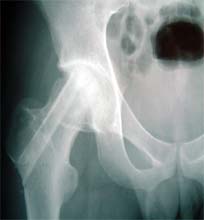

复合骨生长因子和自体骨髓干细胞的新型植骨材料植入支撑,恢复形态, 手术后24个月X线片,关节塌陷未加重,关节功能良好,无疼痛。